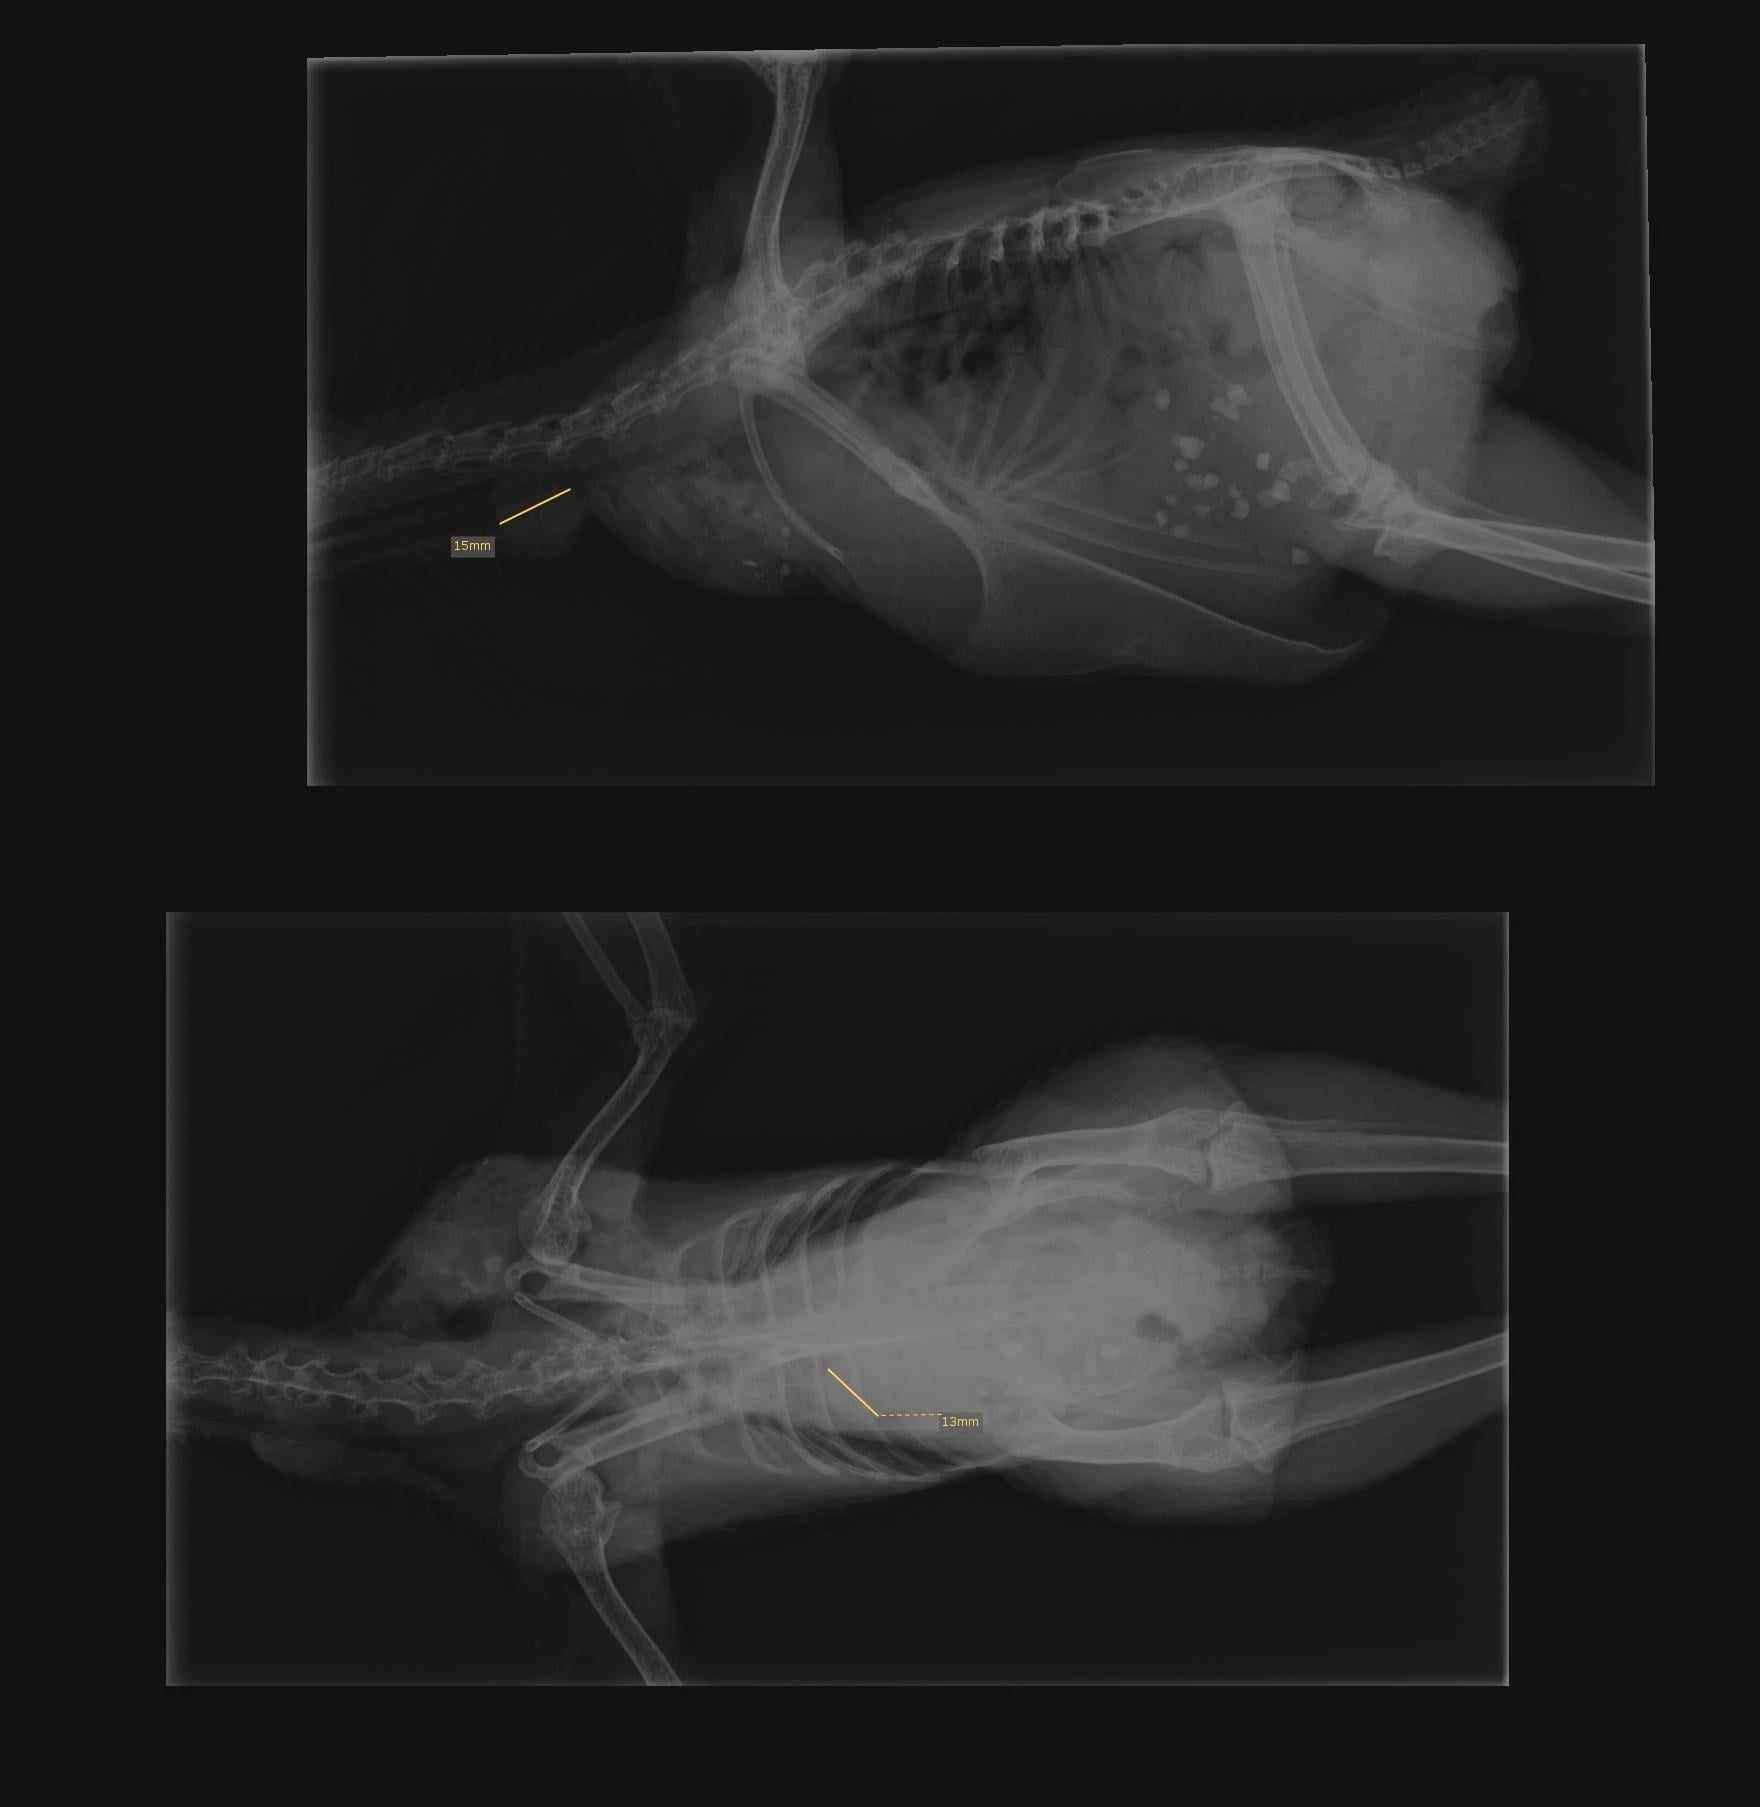

Infektionen spred sig snabbt under hennes sista sju dagar, vilket gjorde det svårt för henne att andas. Trots allt detta gick hon fortfarande fritt och verkade frisk. När vi till slut såg röntgenbilden visste vi att hon bara skulle bli sämre. Vi kunde ha väntat tills tiden kom, men i slutändan valde vi att låta henne få somna in med värdighet.

Här kan ni se de utpekande bölderna vid första röntgen, vid röntgen nr 2 hade de dubblerat sig och satt bland annat på luftsäckarna